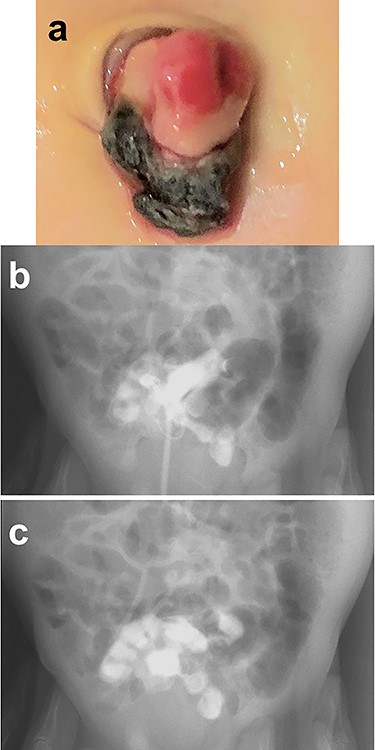

A female infant was born at 37 weeks of gestation, weighing 2068 g. At 31 months of age, her parents noted that she had passed bloody stool twice in the last month (Fig. 3a). She was admitted to the hospital after bloodwork on the day of assessment was compared with routine bloodwork performed 3 months prior and new-onset anemia was noted (Fig. 3b). She underwent nuclear imaging using 99m technetium pertechnetate to investigate the possibility of a Meckel diverticulum. A small, round area of intense tracer activity was noted in the midabdomen, suggesting the presence of ectopic gastric mucosa (Fig. 3c).

Patient workup. (a) Photograph after an episode of bloody stool was noted in the diaper. (b) Bloodwork performed 3 months before admission was normal, while laboratory investigation on the day of assessment reveals new-onset anemia. (c) Nuclear imaging using 99m technetium pertechnetate reveals a small, round area of intense tracer activity in the midabdomen.